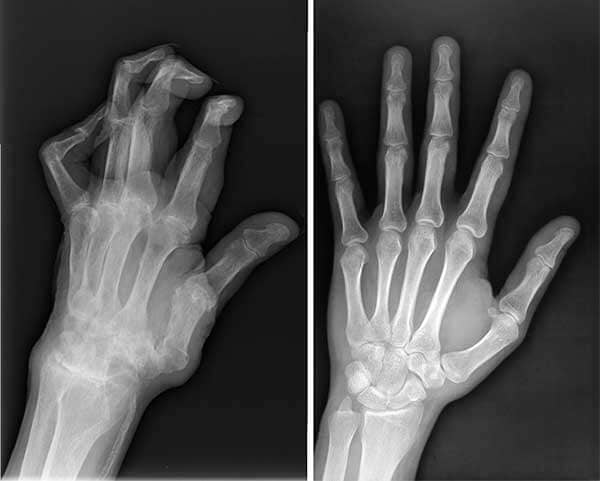

X-ray มือสามีฉันก่อนและหลังใช้ Carthisin

ดูมือเขาตอนนี้ เทียบกับก่อนใช้ ดีขึ้นมากเลย